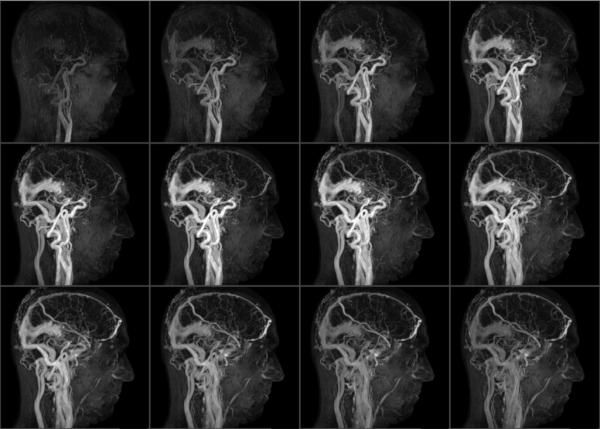

- магнитно-резонансная или компьютерная томография;

При поражении сосудов головного мозга наиболее информативны МРТ и КТ. Дополнительно могут проводиться электроэнцефалография и электрокардиография. При поражении мозговых артерий может понадобиться консультация офтальмолога и невролога.

Основным признаком атеросклероза является сужение артерий. Бляшки диагностируются в процессе магнитно-резонансной томографии. Ее преимущества:

точность;

- информативность;

- возможность осмотреть стенки артерий;

- отсутствие лучевой нагрузки;

- безопасность;

- безболезненность.

Томография абсолютно противопоказана людям с различными металлическими и электронными имплантами (клипсами, кардиостимуляторами) и в случае развития гемопоэтической анемии.

Для повышения информативности исследования предварительно внутривенно вводится контраст. Чаще всего применяются средства на основе редкоземельных металлов.